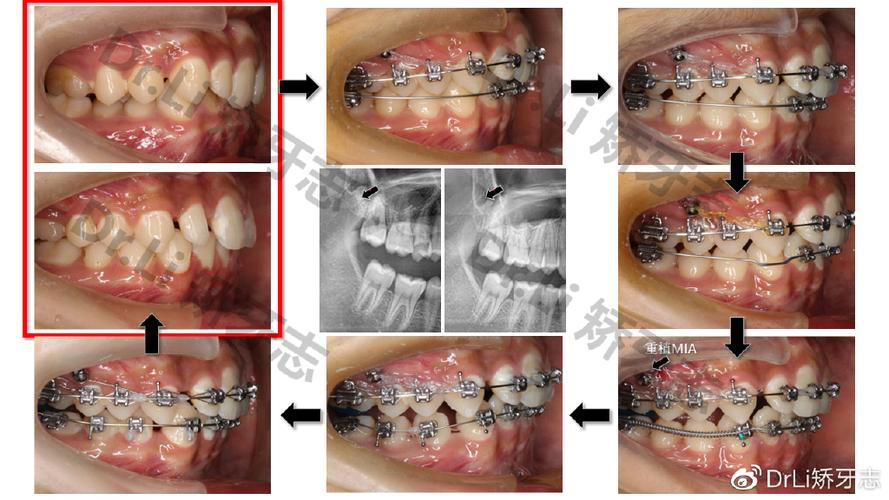

作用机制:在固定矫治器(如方丝弓、直丝弓矫治器)基础上,于磨牙与前牙间放置镍钛螺旋弹簧或不锈钢螺旋弹簧,利用弹簧展开产生的持续力推动磨牙远移,需通过腭杆、舌弓或种植支抗加强后牙支抗。

操作要点:弹簧力值控制在100-200g,每4周更换一次,移动过程中需用弓丝弯制“后倾弯”控制磨牙倾斜。

适应证:上下颌磨牙均可适用,尤其适用于牙弓轻度拥挤、需少量远移(<4mm)的病例。

优缺点:优点为操作简便,可精确控制力值;缺点是支抗要求高,若支抗不足易导致前牙前突,远移速度较慢(0.5-1mm/月)。